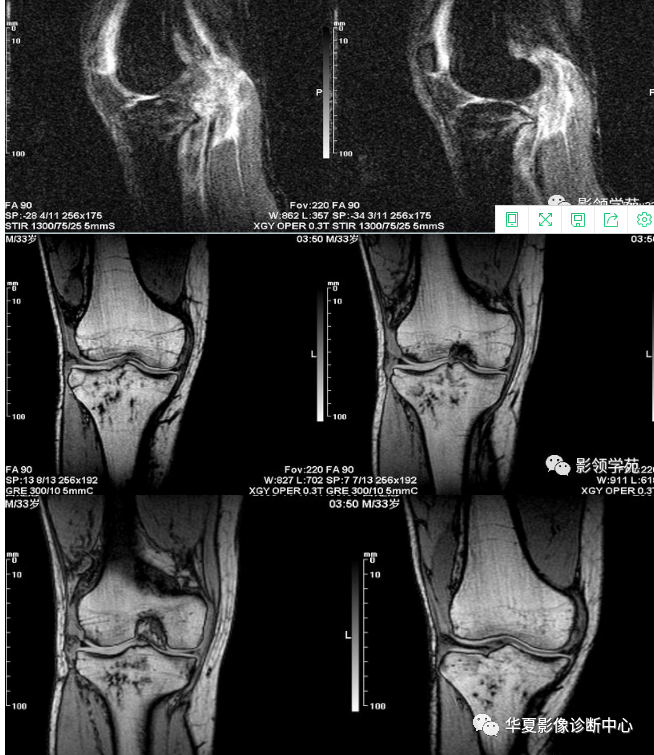

MRI诊断隐性骨折的意义

骨信号的情况 隐性骨折在低场MRI表现为:T1WI序列上见由关节面向骨干走行的形态各异低信号区,有线状、条状、紊乱低信号,信号强度不均匀;与T1WI低信号改变相对应部位在T2WI上表现为相应形状的高、低混杂信号,且部分低信号周围可见高信号水肿改变。STIR序列图像上病灶呈显著高信号,与信号被抑制的临近正常骨髓形成鲜明对比,分界也较T2WI成像更为清楚。

隐性骨折的病理与MRI信号改变

隐性骨折主要病理学改变为骨小梁断裂,无骨皮质中断,并伴有局部骨松质内水肿和出血。无骨皮质中断,尚不足以引起X线衰减系数的明显改变,X线平片无异常征象;CT在显示骨皮质及软组织异常方面明显优于传统X线,特别是三维重建能够有效的评价复杂骨折,骨外伤CT检查应用广泛,但CT对隐性骨折的显示亦极为有限。

由外力作用使骨髓局部充血,毛细血管床过渡灌注而致骨髓水肿,水肿时自由水增加,一系列骨组织局部的化学成份变化导致了MRI驰豫时间发生变化,产生MRI信号异常改变。T2WI及压脂序列成高信号影,这信号改变代表着骨髓细胞外液的增多,而细胞外液的增多的程度和数量又决定着水肿所致异常信号的强弱和范围[4]。转组织抑制技术是MRI的一个重要性能,脂肪抑制技术在MRI应用中可以改善组织对比和增加病变显示机会,这样骨髓的脂肪抑制后就不会有任何信号,而隐性骨折线及骨髓水肿的异常高信号就会更加明显的显示出来。